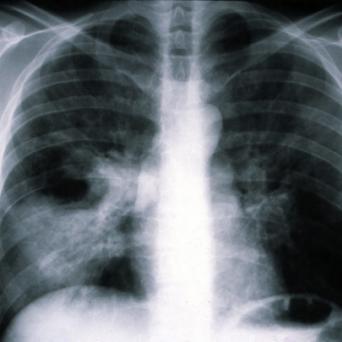

Les personnes souffrant de TCA – anorexie, boulimie, hyperphagie boulimique – ont un risque accru de mortalité par suicide ou par troubles métaboliques par rapport à la population générale. Plus le repérage est précoce, meilleur est le pronostic. Quels sont les facteurs de risque et les changements de comportement évocateurs ? Quel bilan initial ? Quelle prise en charge ?